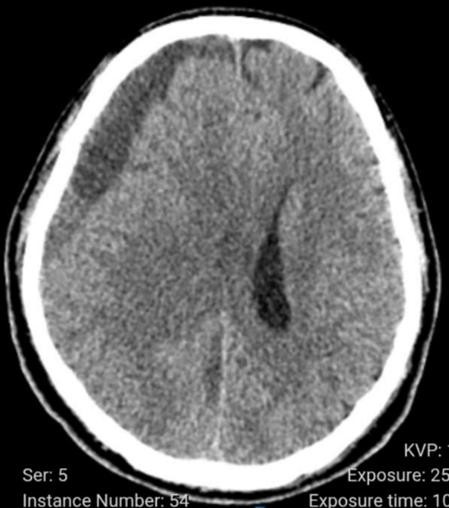

Tràn mủ dưới màng cứng trên phim chụp - Ảnh BVCC

Tuy nhiên, khi các triệu chứng tiến triển nặng, bác sĩ đã chỉ định chụp cắt lớp vi tính lần 2, phát hiện khối dịch mủ hỗn hợp dưới màng cứng vùng trán – đỉnh não phải, gây đè đẩy não, lệch đường giữa và chèn ép não thất.